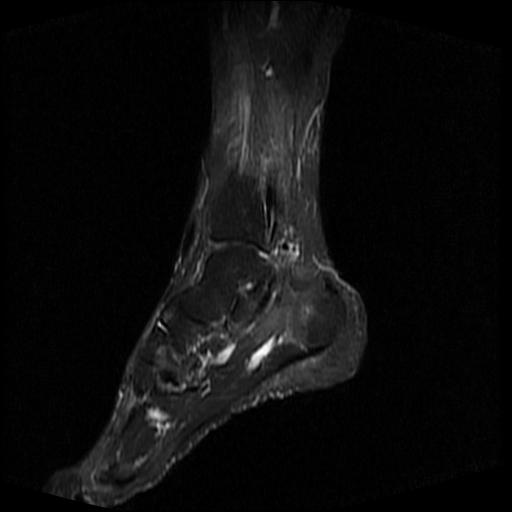

标题: MRI0968:女性,70岁,跟骨信号异常 [打印本页]

标题: MRI0968:女性,70岁,跟骨信号异常

女性,70岁,右侧跟骨疼痛2个月,负重时加剧,不负重时不疼。

跟骨慢性炎症.伴脓肿形成.

考虑  跟骨骨髓炎

跟骨病灶呈片状,边界模糊,可否考虑隐匿性骨折呢?

跟骨长t1长t2信号异常,边缘模糊(肿瘤一般边界清楚,故肿瘤不考虑),压脂像呈高信号--骨髓水肿(炎症?)。